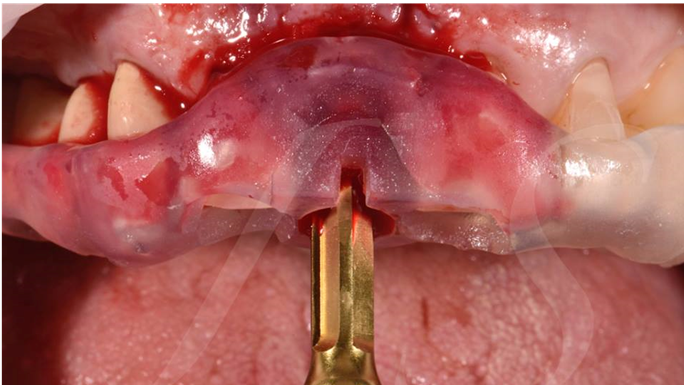

“ One implant /One tooth/ One hour step-by-step

+ associated connective graft ”

Clinical case: EImmediate implant placement & loading of #35 extraction socket with defect

- Courtesy of Dr. Kwang Bum Park, Korea -

Dr. Laurent Sers, immediate loading, digital guided surgery, digital ONE-DAY implant, maxillary anterior, #21, guided surgery, immediate loading, AnyRidge, R2GATE, Mega ISQ, R2GATE Full Surgical Kit

implant system, R2GATE Guide, R2GATE surgical kit (AnyRidge), Mega ISQ